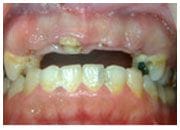

治療前

陳小姐正值二十出頭花樣年華,但是小時候做的牙橋,裡面的牙根己經腐壞,假牙搖搖欲墬,陳小姐雖然年紀輕輕,但是上排的牙齒所剩無幾,經過本診所人工植牙治療,陳小姐一改當初害羞不敢啟齒的個性,每次回診都是笑容滿面,陳小姐感謝黃醫師讓她重拾應有的青春美麗。